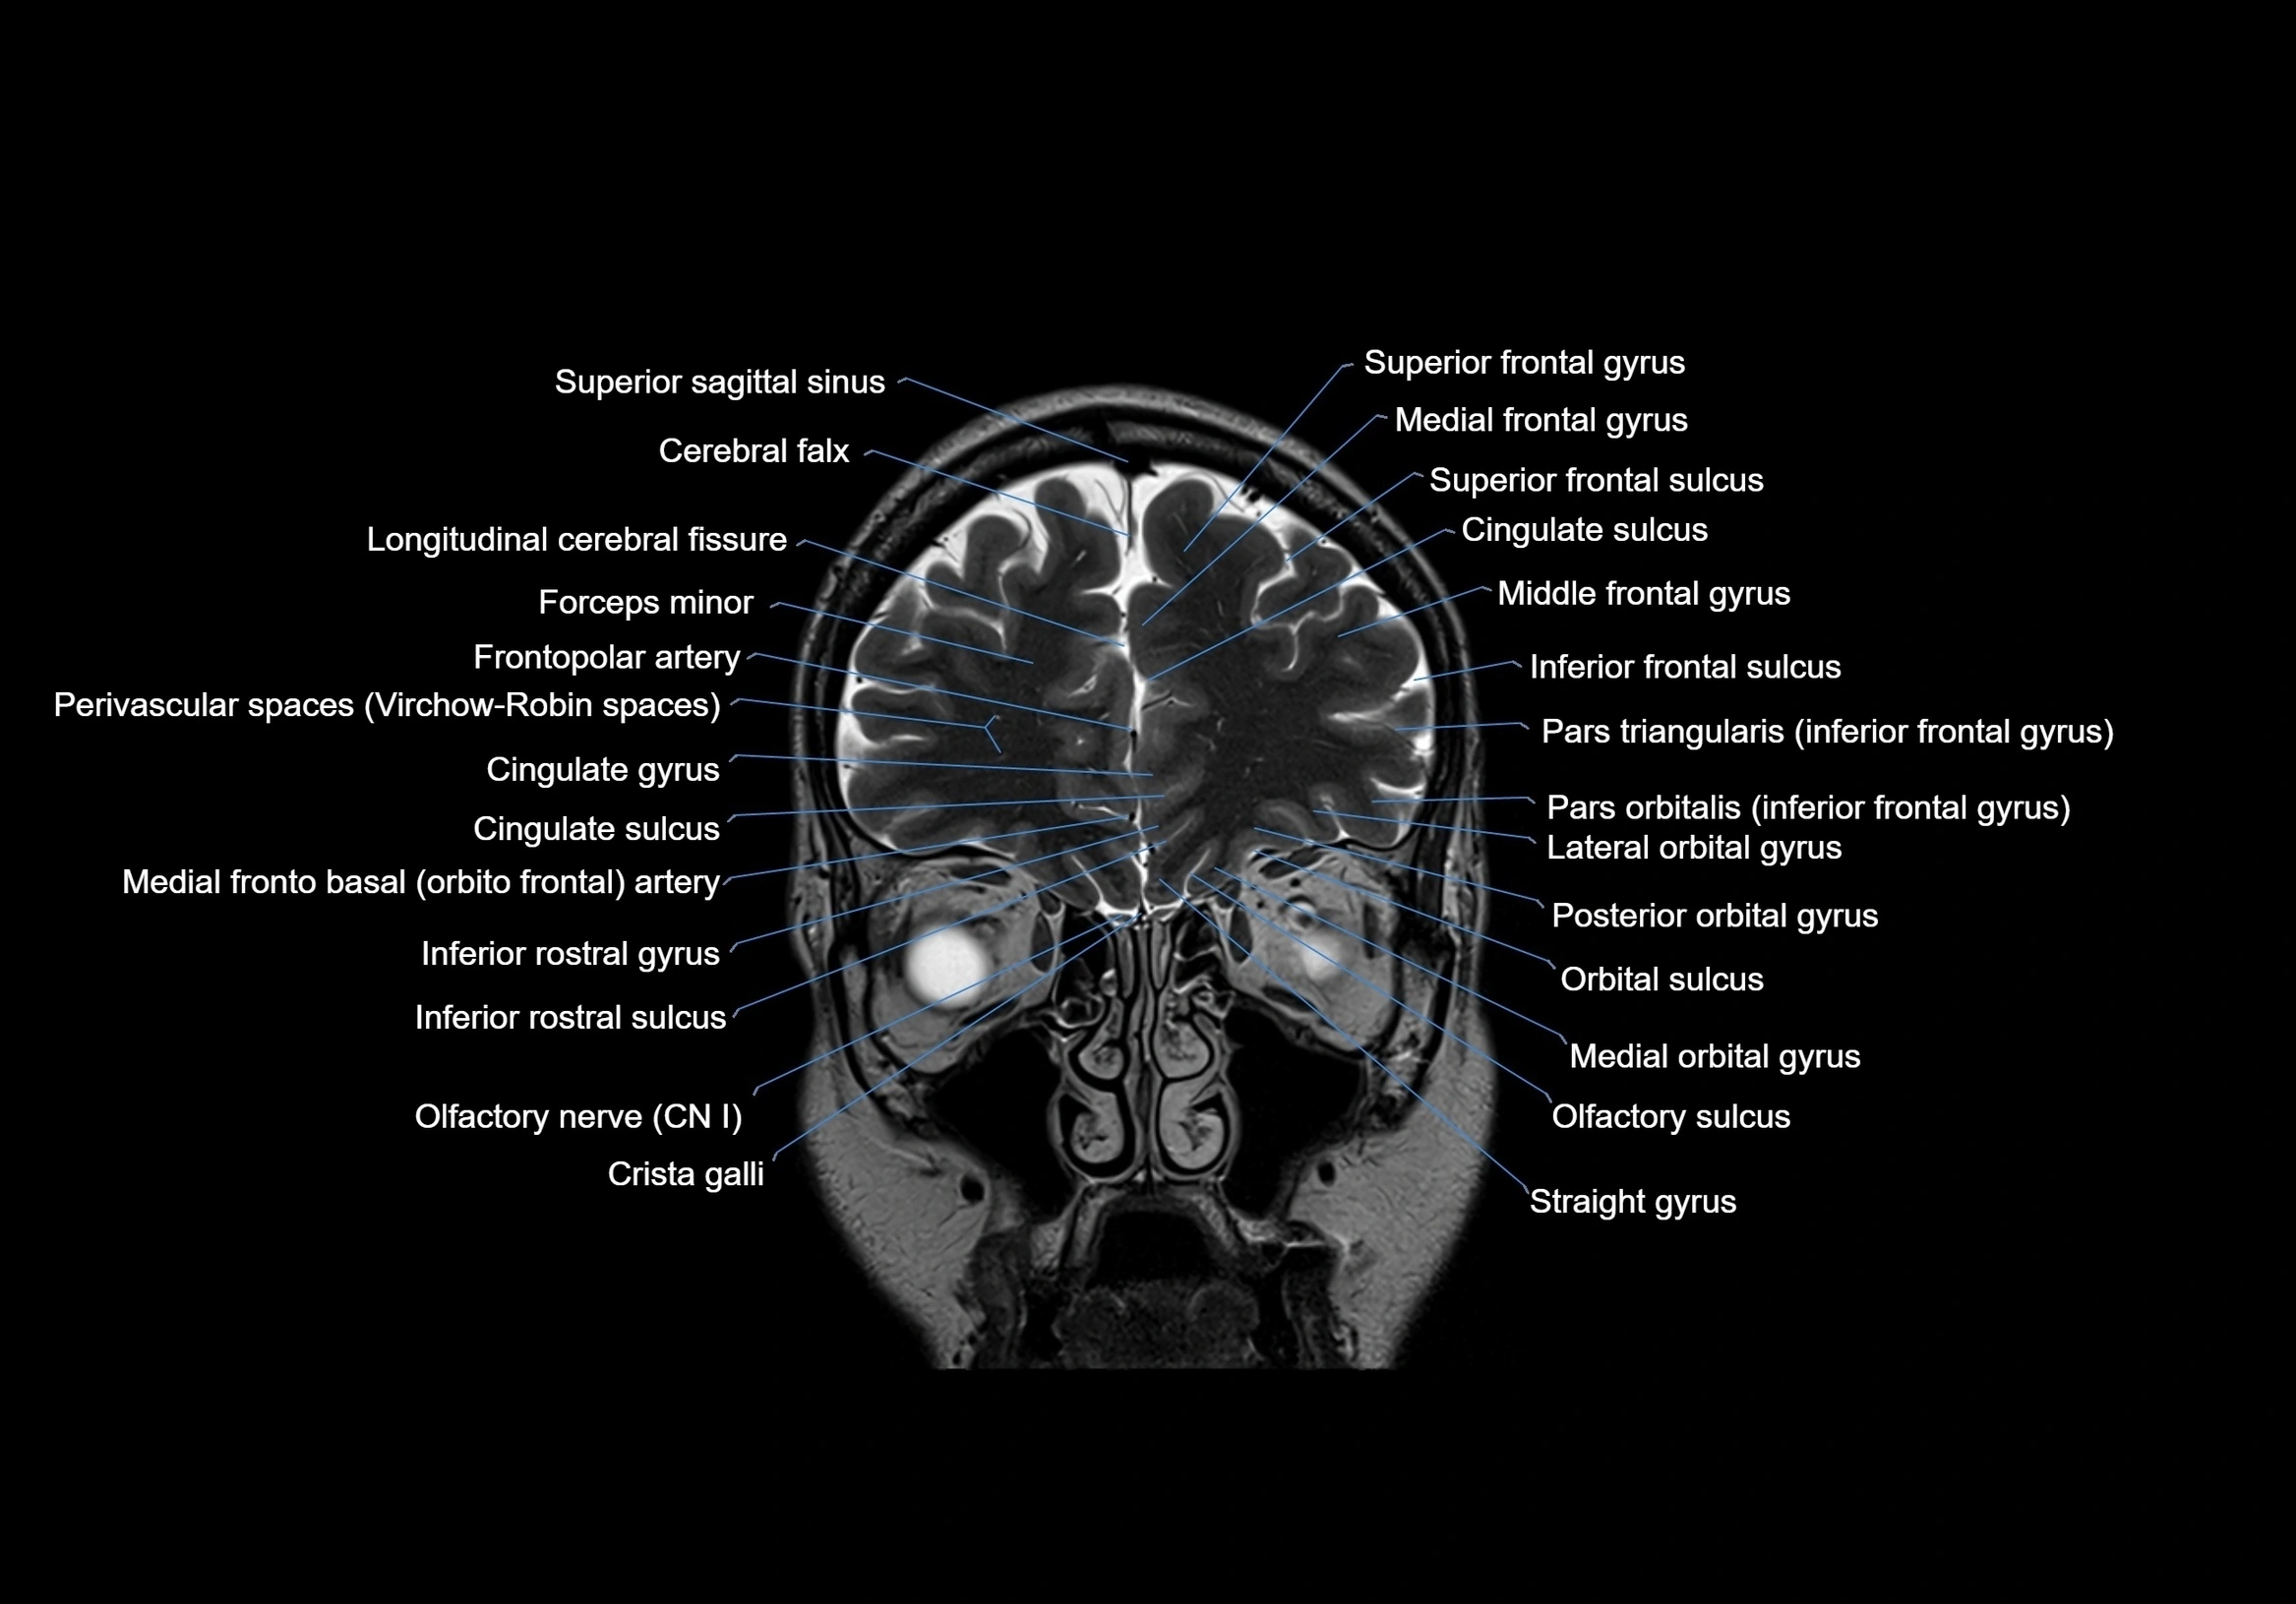

MRI images